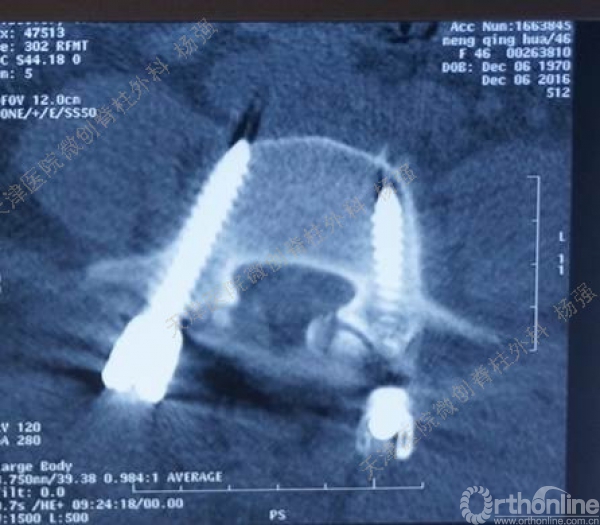

腰5椎体前滑脱I-II°,峡部裂,动力位显示腰5-骶1节段明显失稳

CT、MRI示:腰5椎体前滑脱,腰5/骶1水平间盘突出,腰5双侧椎弓峡部裂